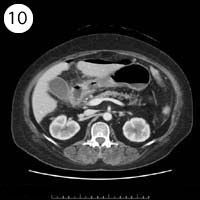

57歳 女性

単純CT

造影CT